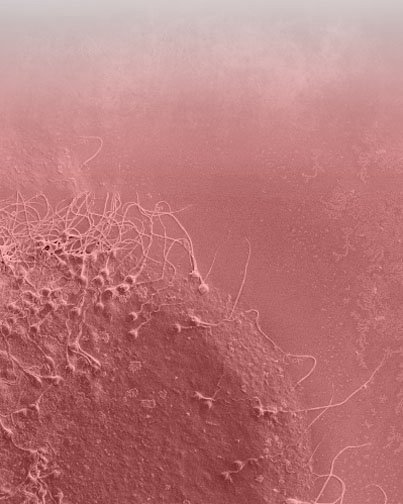

ich möchte Ihnen für Ihre freundliche telefonische Auskunft am vergangenen Montag, den 25. Januar, über die genetische Beratung vor der Implantation danken (PID ohne Ergebnisse wegen Problemen durch DNA-Verstärkung in einem anderen Zentrum).